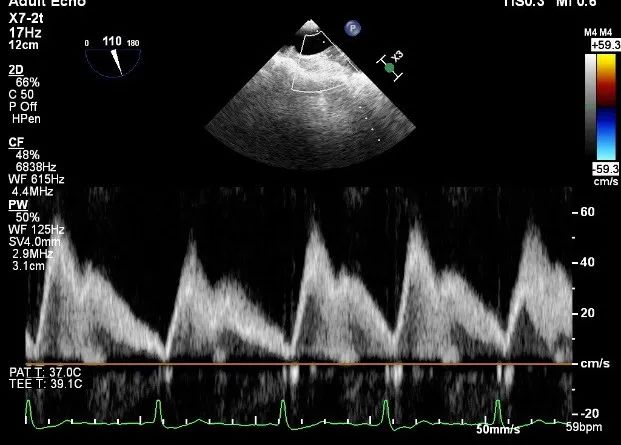

确定房间隔穿刺点:靠后

2D视图下测量大鞘长度2cm

3D视图打开夹子

X-plane:下第夹子尝试捕获2区

X-plane:测量前叶长25mm,后叶长14.2mm

X-plane:计算前叶捕获长度8mm,后叶捕获长度7mm

3D视图下观察二尖瓣双孔形态

3D-color:残余少量返流